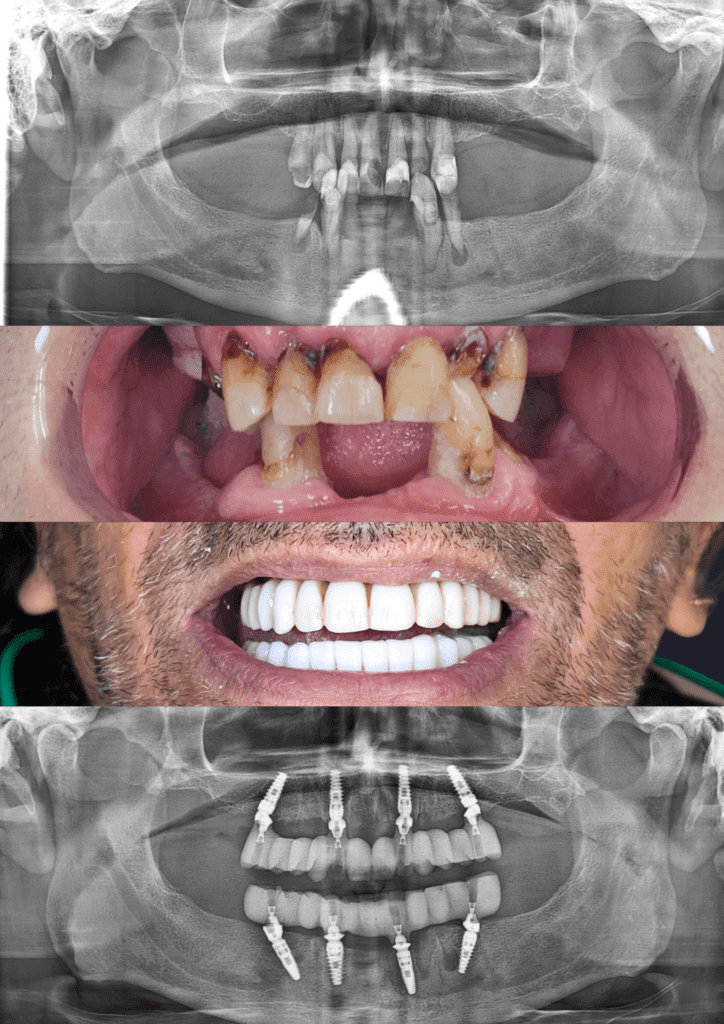

Before & After Treatment Gallery

The photos shown here document completed full-jaw implant treatments. Each case involved detailed planning, surgical placement of implants, and a custom-made fixed bridge. Treatment outcomes, timelines, and suitability vary and are assessed on a case-by-case basis.